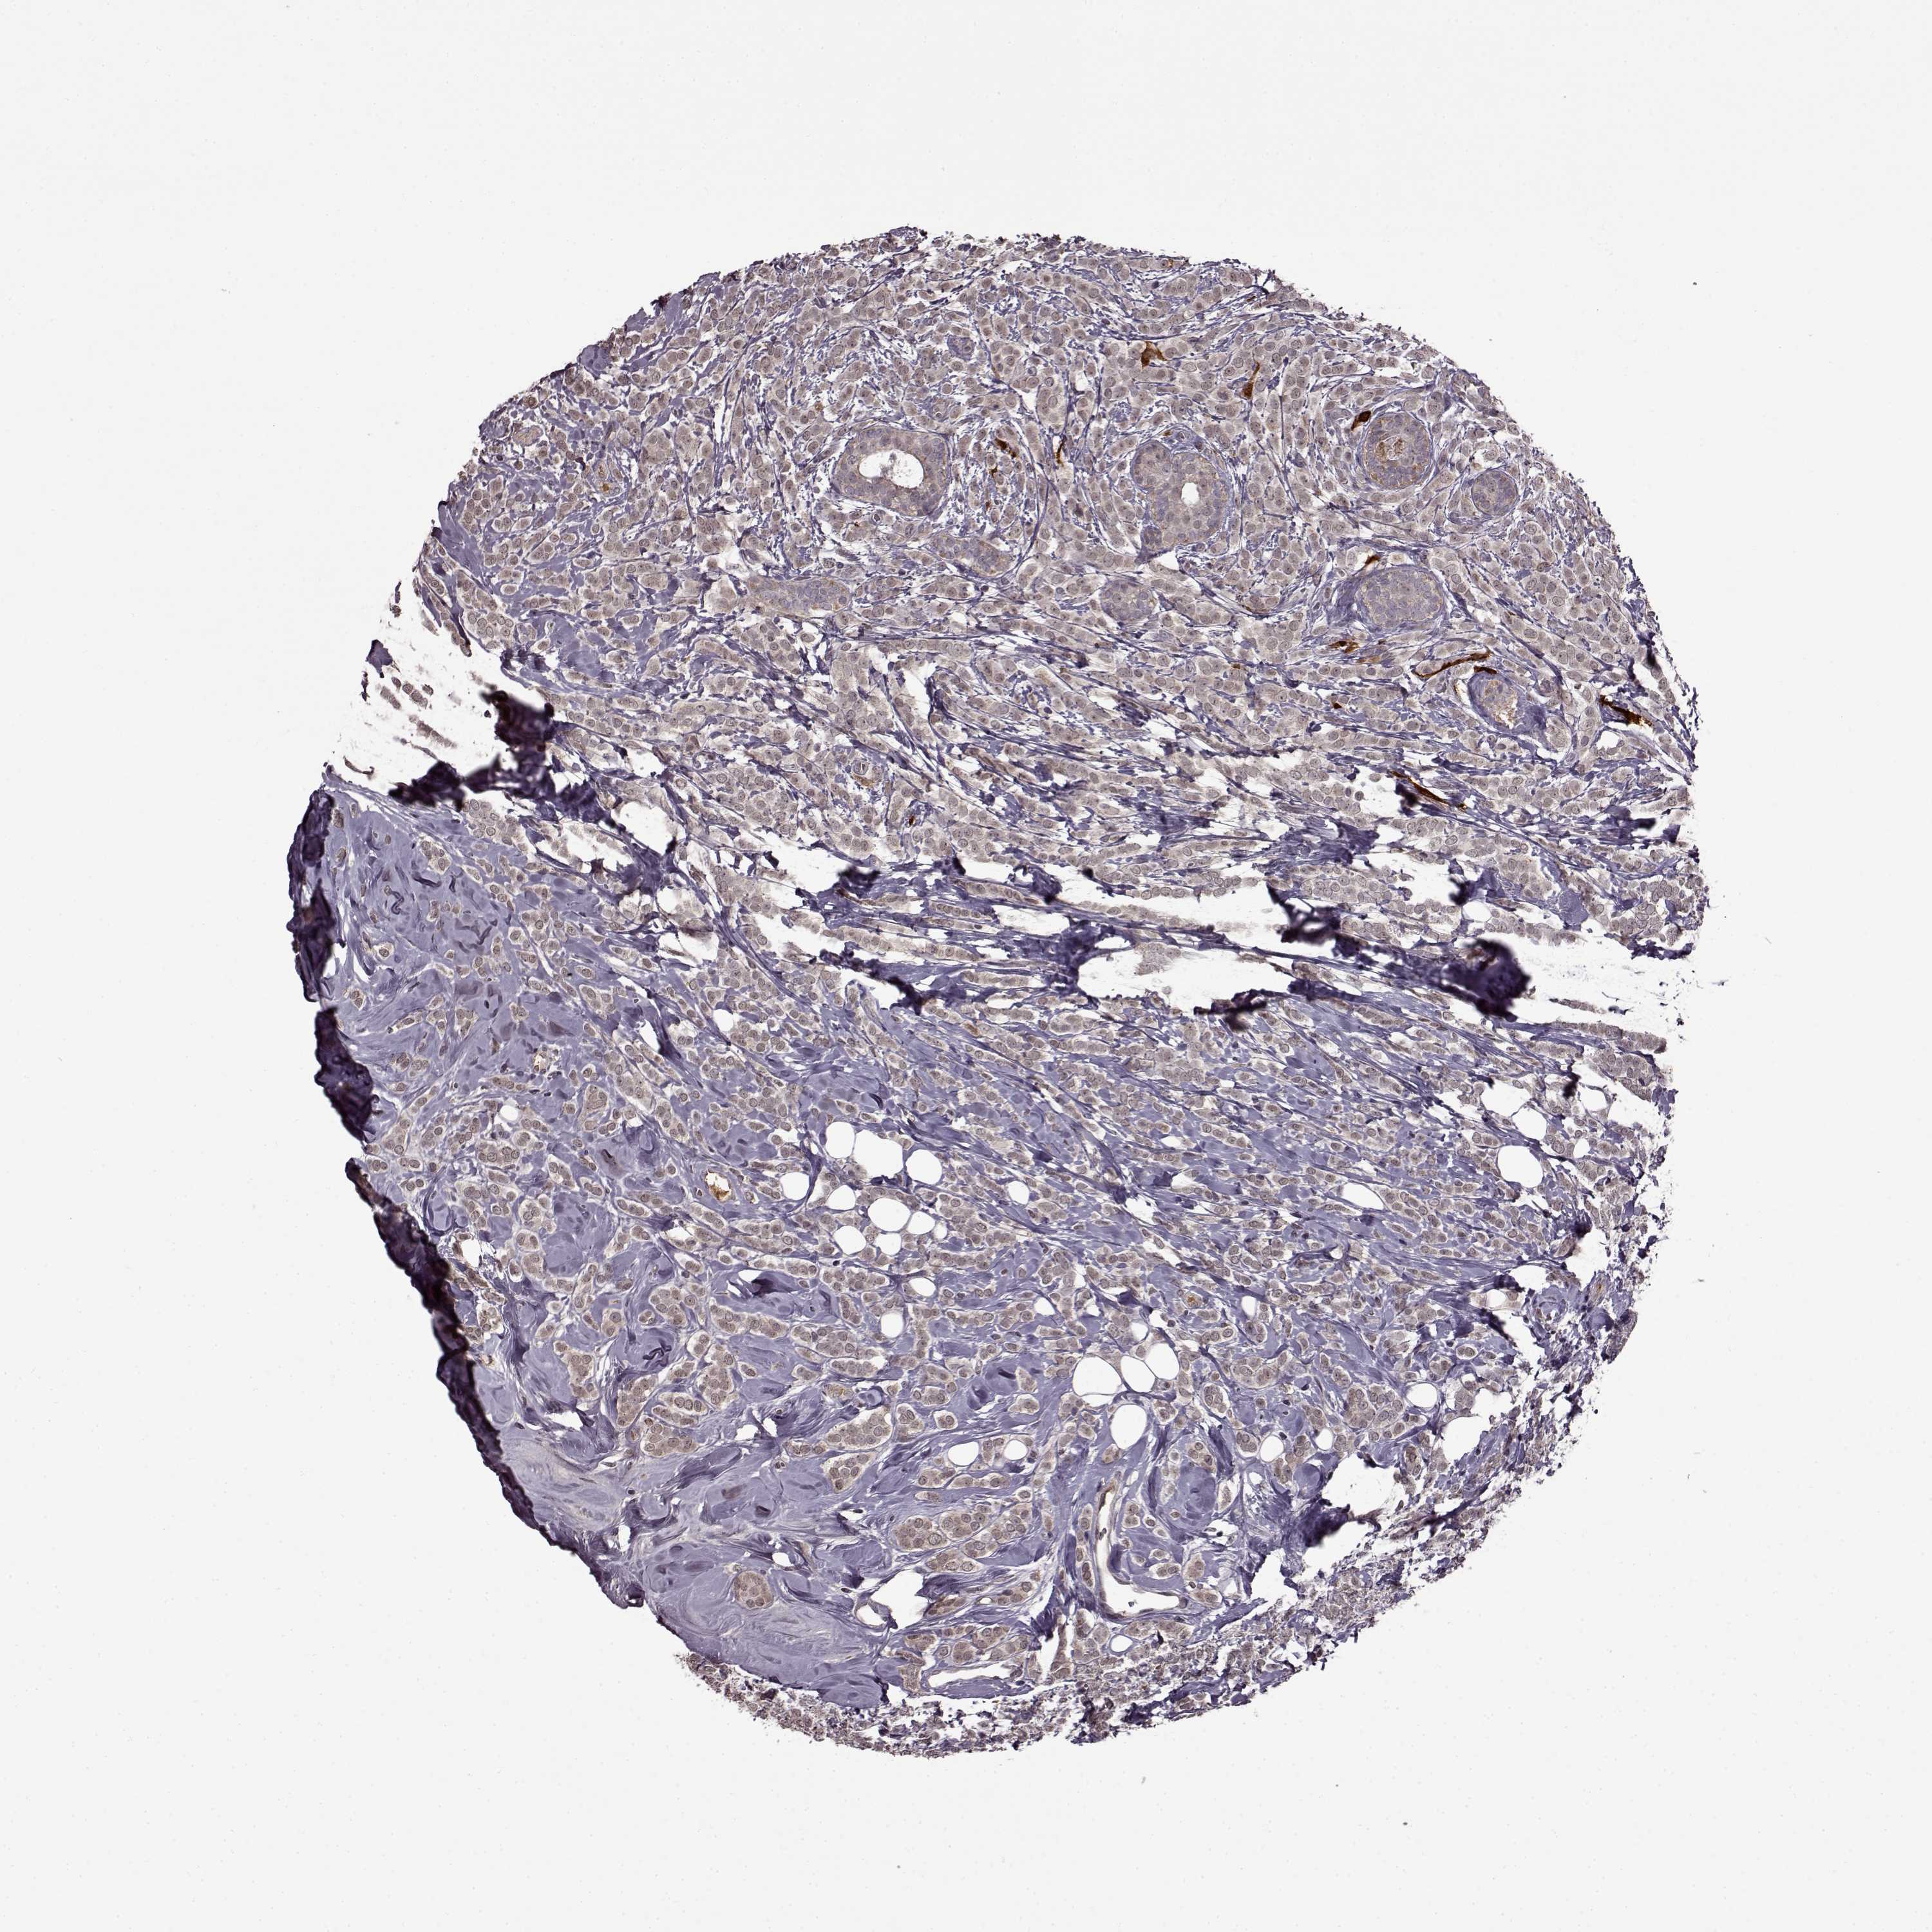

CANCER BREAST CANCER Show tissue menu

BRCA TCGA BRCA VALIDATION PROTEIN EXPRESSION